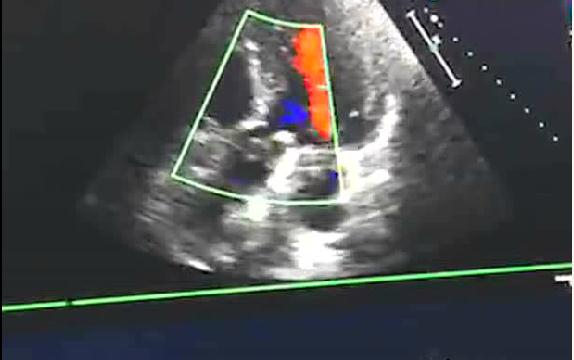

術(shù)后彩超復(fù)查結(jié)果

患者本人及家屬?gòu)?qiáng)烈要求找到一種既能手術(shù)、術(shù)后又無(wú)需服藥的治療方法,解放軍第210醫(yī)院心胸外科曹輝主任仔細(xì)研究病例后,建議患者行主動(dòng)脈瓣膜成形手術(shù),術(shù)后無(wú)需終身口服抗凝藥,患者及家屬欣然接受。經(jīng)與北京安貞醫(yī)院孟旭主任(國(guó)內(nèi)外知名心血管外科專家)遠(yuǎn)程會(huì)診及協(xié)商后,擬行“應(yīng)用自體心包主動(dòng)脈瓣瓣膜成形手術(shù)”。6月30日,在專家的協(xié)助下手術(shù)順利完成,目前恢復(fù)良好,術(shù)后1周活動(dòng)正常,復(fù)查心臟超聲提示主動(dòng)脈成形瓣膜功能良好,無(wú)明顯血液返流。